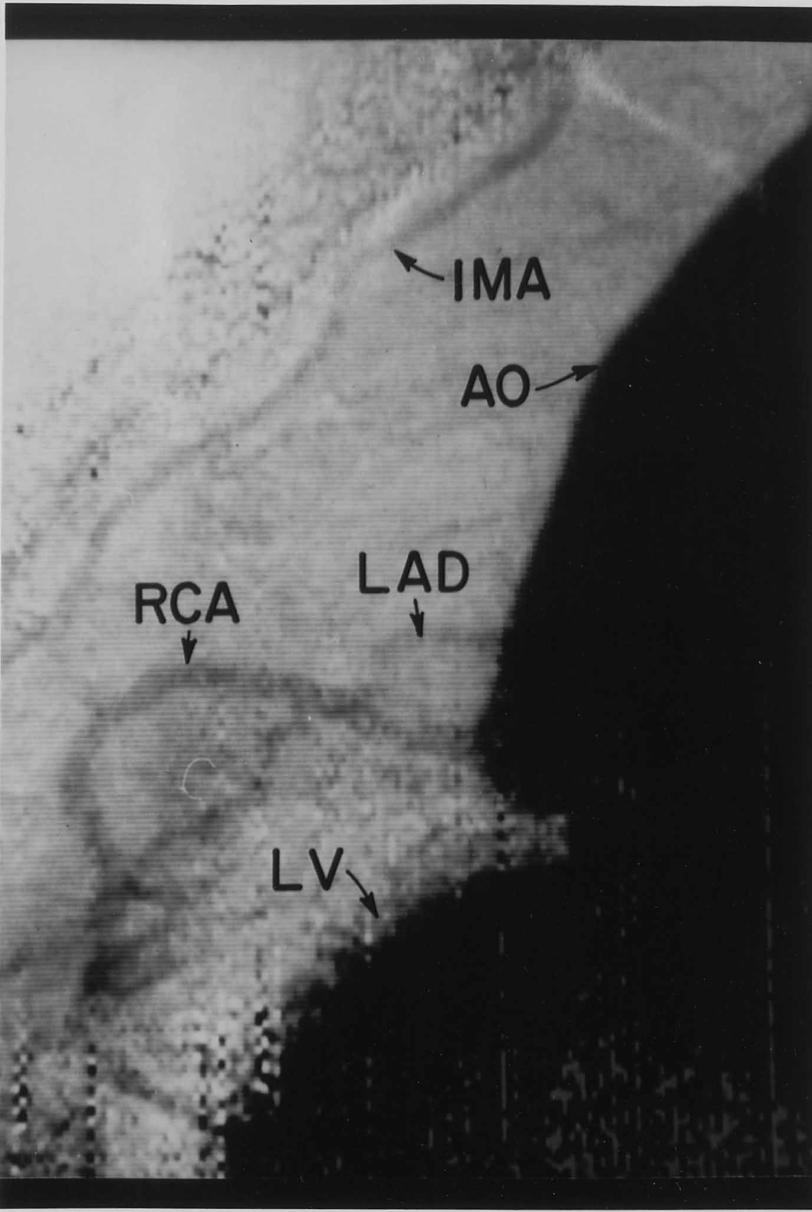

The first synchrotron radiation coronary angiogram recorded on a human subject occurred in May 1986 at the Stanford Synchrotron Radiation Laboratory (SSRL). The study is believed to have been the first synchrotron radiation imaging procedure performed on a human being. As of 2002, some 500 intravenous coronary angiograms had been recorded at SSRL, NSLS, DESY, and ESRF, all without complication. By 2010, the American Heart Association reports that over 600,000 such procedures are being performed annually in the United States. (In the angiogram, the following structures are identified: AO, ascending aorta; LV, left ventricle; IMA, internal mammary artery; LAD, left anterior descending coronary artery; RCA, right coronary artery.)

In the angiogram, the following structures are identified: AO, ascending aorta; LV, left ventricle; IMA, internal mammary artery; LAD, left anterior descending coronary artery; RCA, right coronary artery. (SSRL)